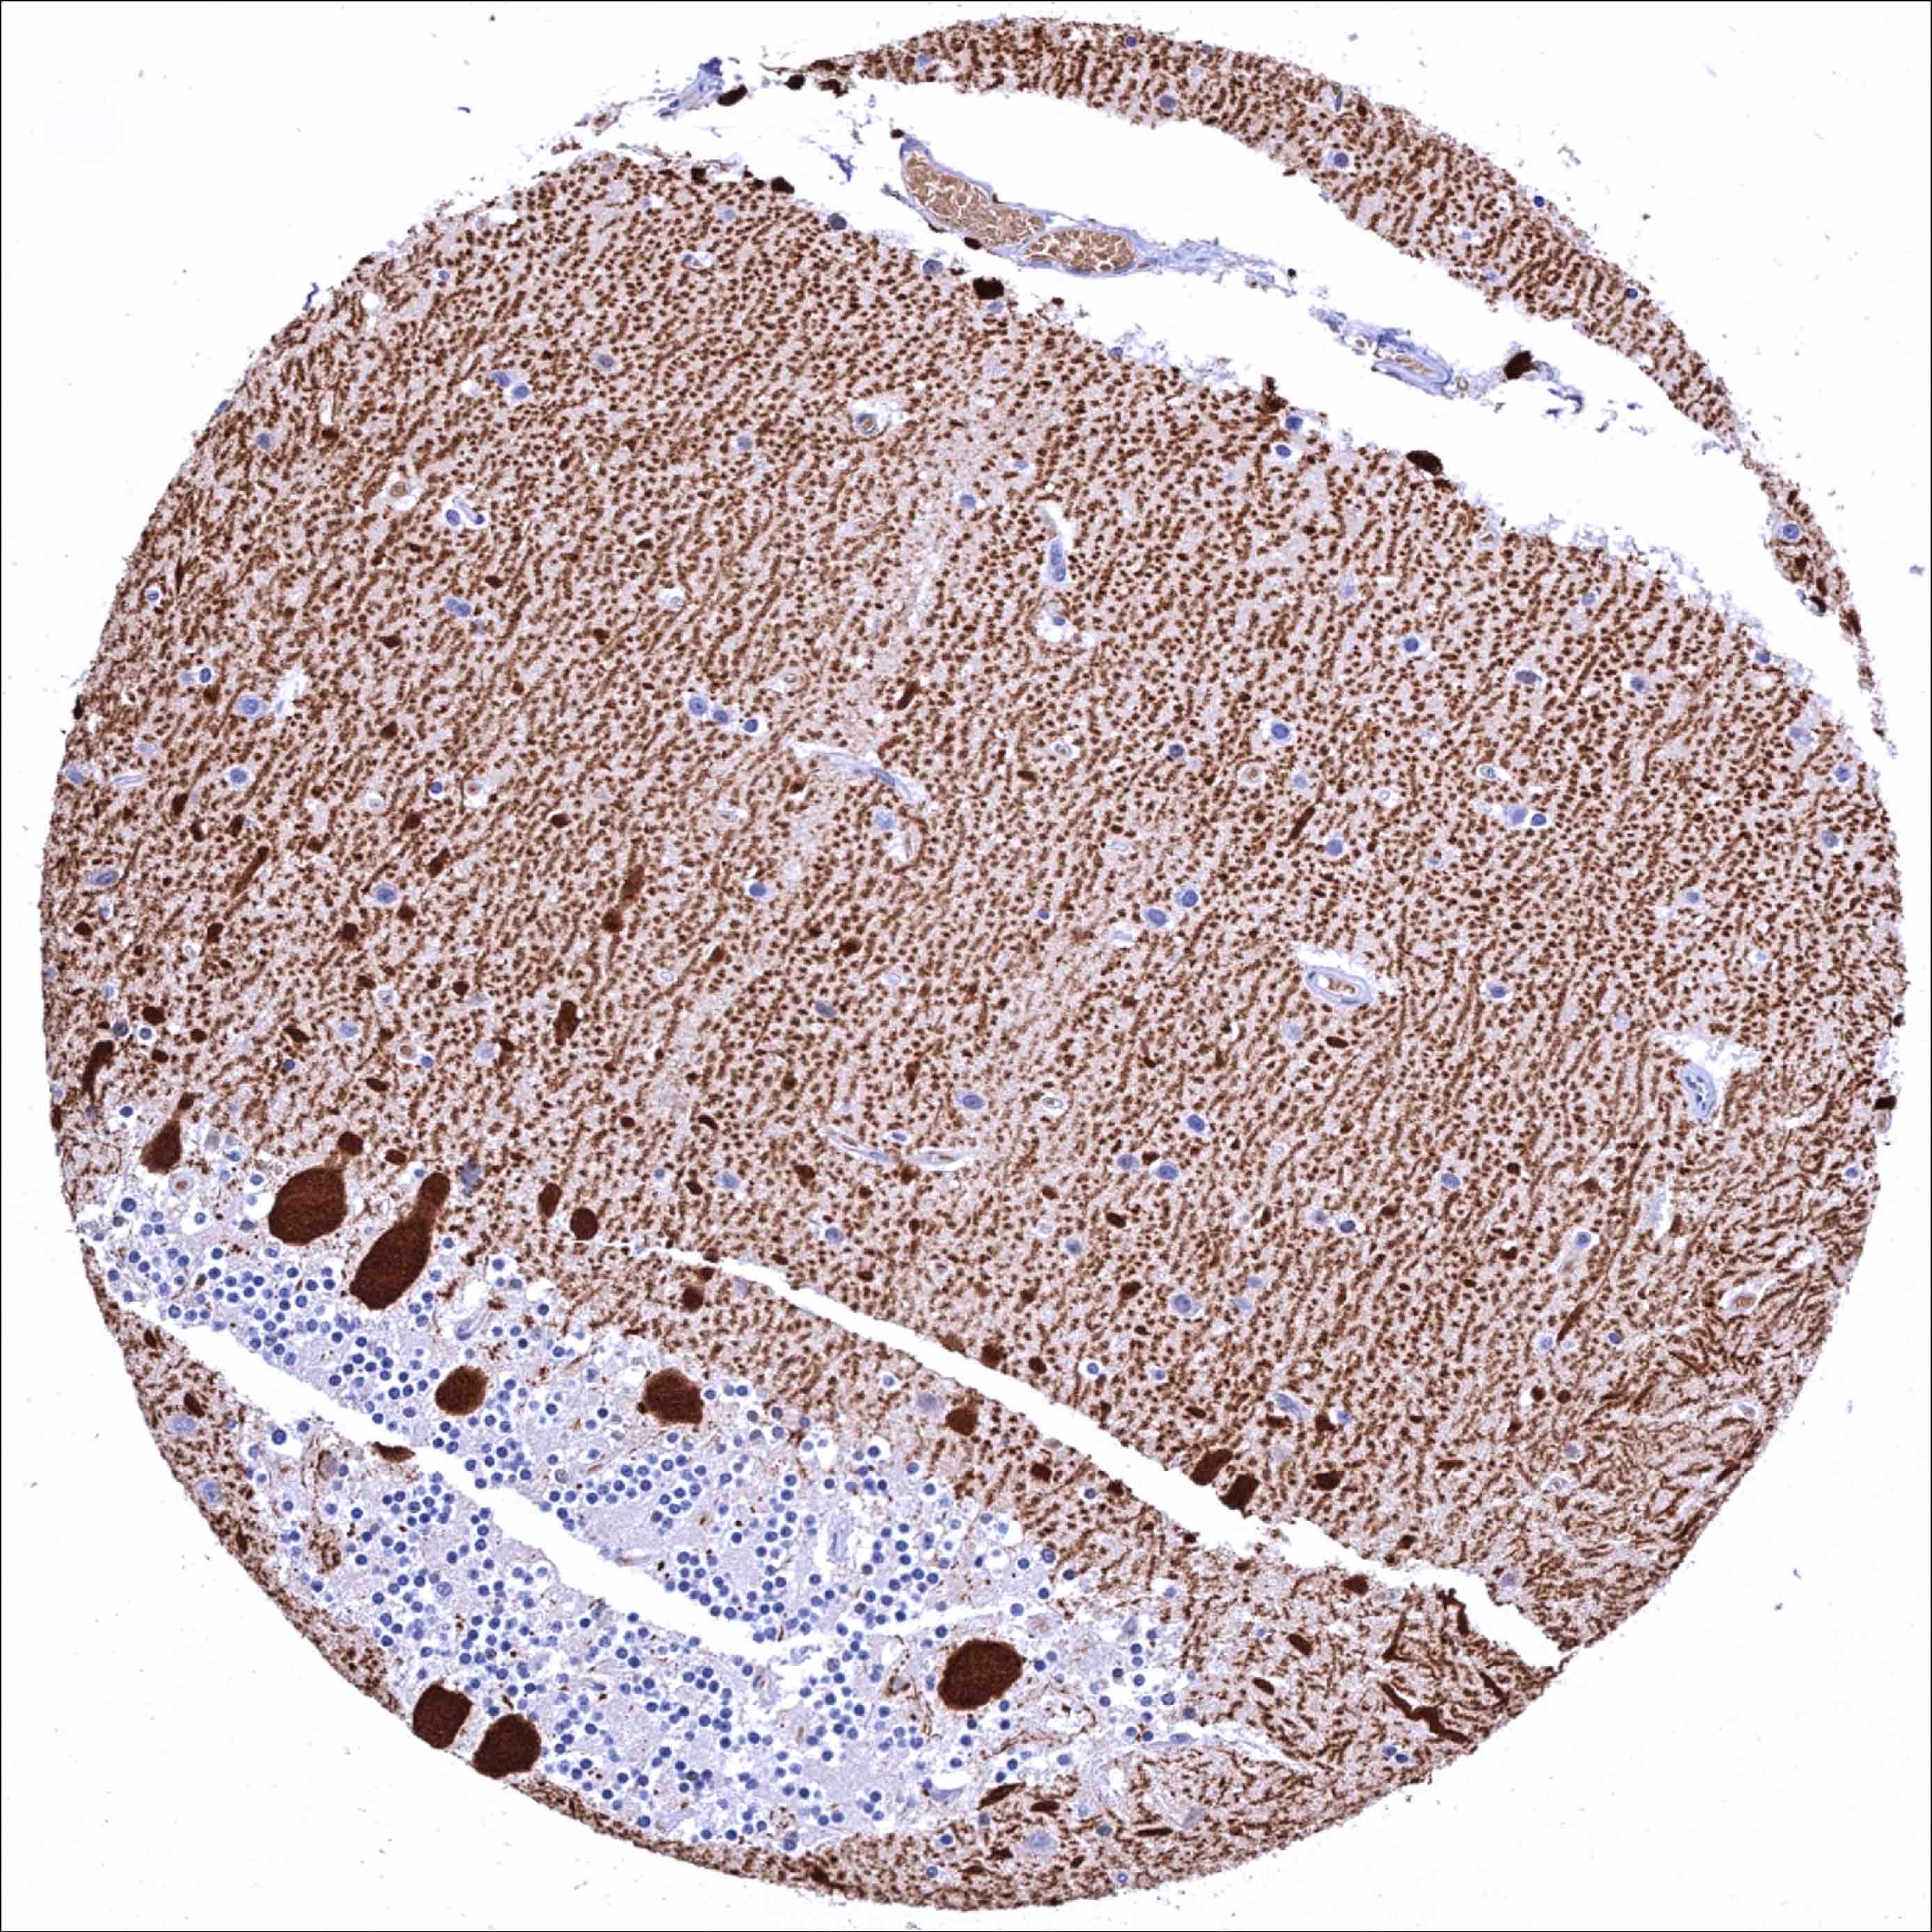

Cerebellum (white matter) – Strong Calbindin 1 staining of axonal fibres

Cerebellum, cortex (molecular layer, Purkinje cell layer, granule cell layer) – Strong Calbindin 1 staining of Purkinje cells and of associated axonal fibres.